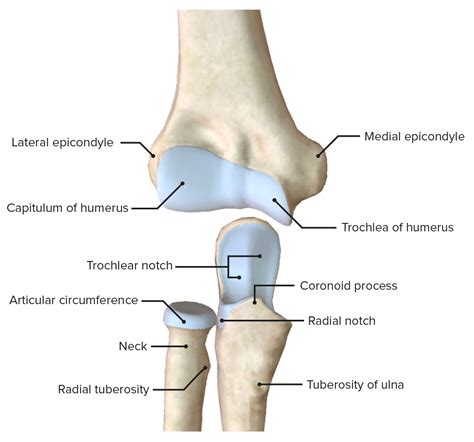

The elbow joint is a hinge joint that allows for flexion and extension of the forearm. It is formed by the articulation of three bones: the humerus, ulna, and radius. The humerus is the long bone of the upper arm, while the ulna and radius are the bones of the forearm.

• Humerus: The upper arm bone that forms the upper part of the elbow joint.

• Ulna: The larger of the two forearm bones, which forms the medial (inner) part of the elbow joint.

• Radius: The smaller of the two forearm bones, which forms the lateral (outer) part of the elbow joint.

• elbow bones diagram

• elbow joint anatomy labeled

• elbow diagram

• elbow joint structure diagram